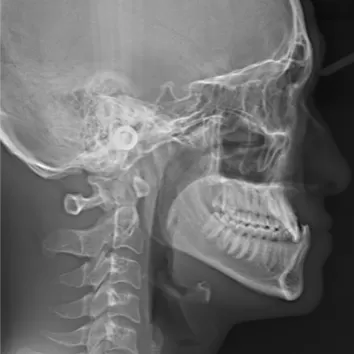

X-rays before treatment

[Panoramic Radiography/Lateral Cephalogram]